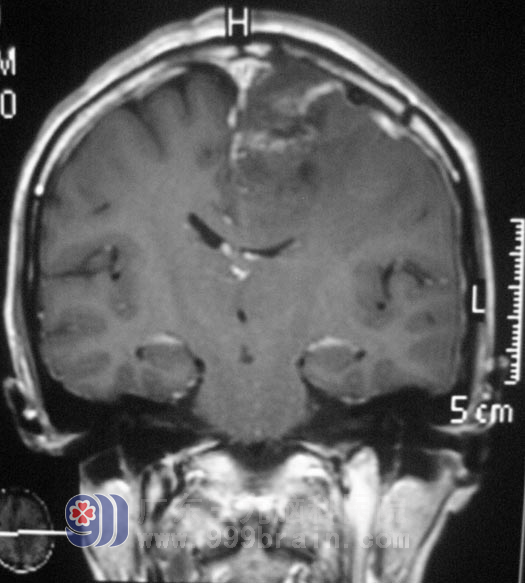

经过一段时间的休养,阿花在家人的陪同下住进了广东三九脑科医院综合神经外科,鲁明主任亲自为她行左侧额顶大脑镰旁占位病变切除术,肿瘤位于矢状窦左侧,表面回流静脉充盈,并向矢状窦汇集,沿肿瘤边界向大脑镰仔细分离并切除肿瘤,肿瘤血供稍丰富,向额叶方向分离后见肿瘤供血动脉,沿肿瘤边界分离,全切肿瘤,将大脑镰壁上残留肿瘤组织清扫。手术后她的病情稳定,恢复得很好,病理结果是:(左侧额顶部)脑膜瘤,WHOI 级。http://www.999brain.com/

▲手术后